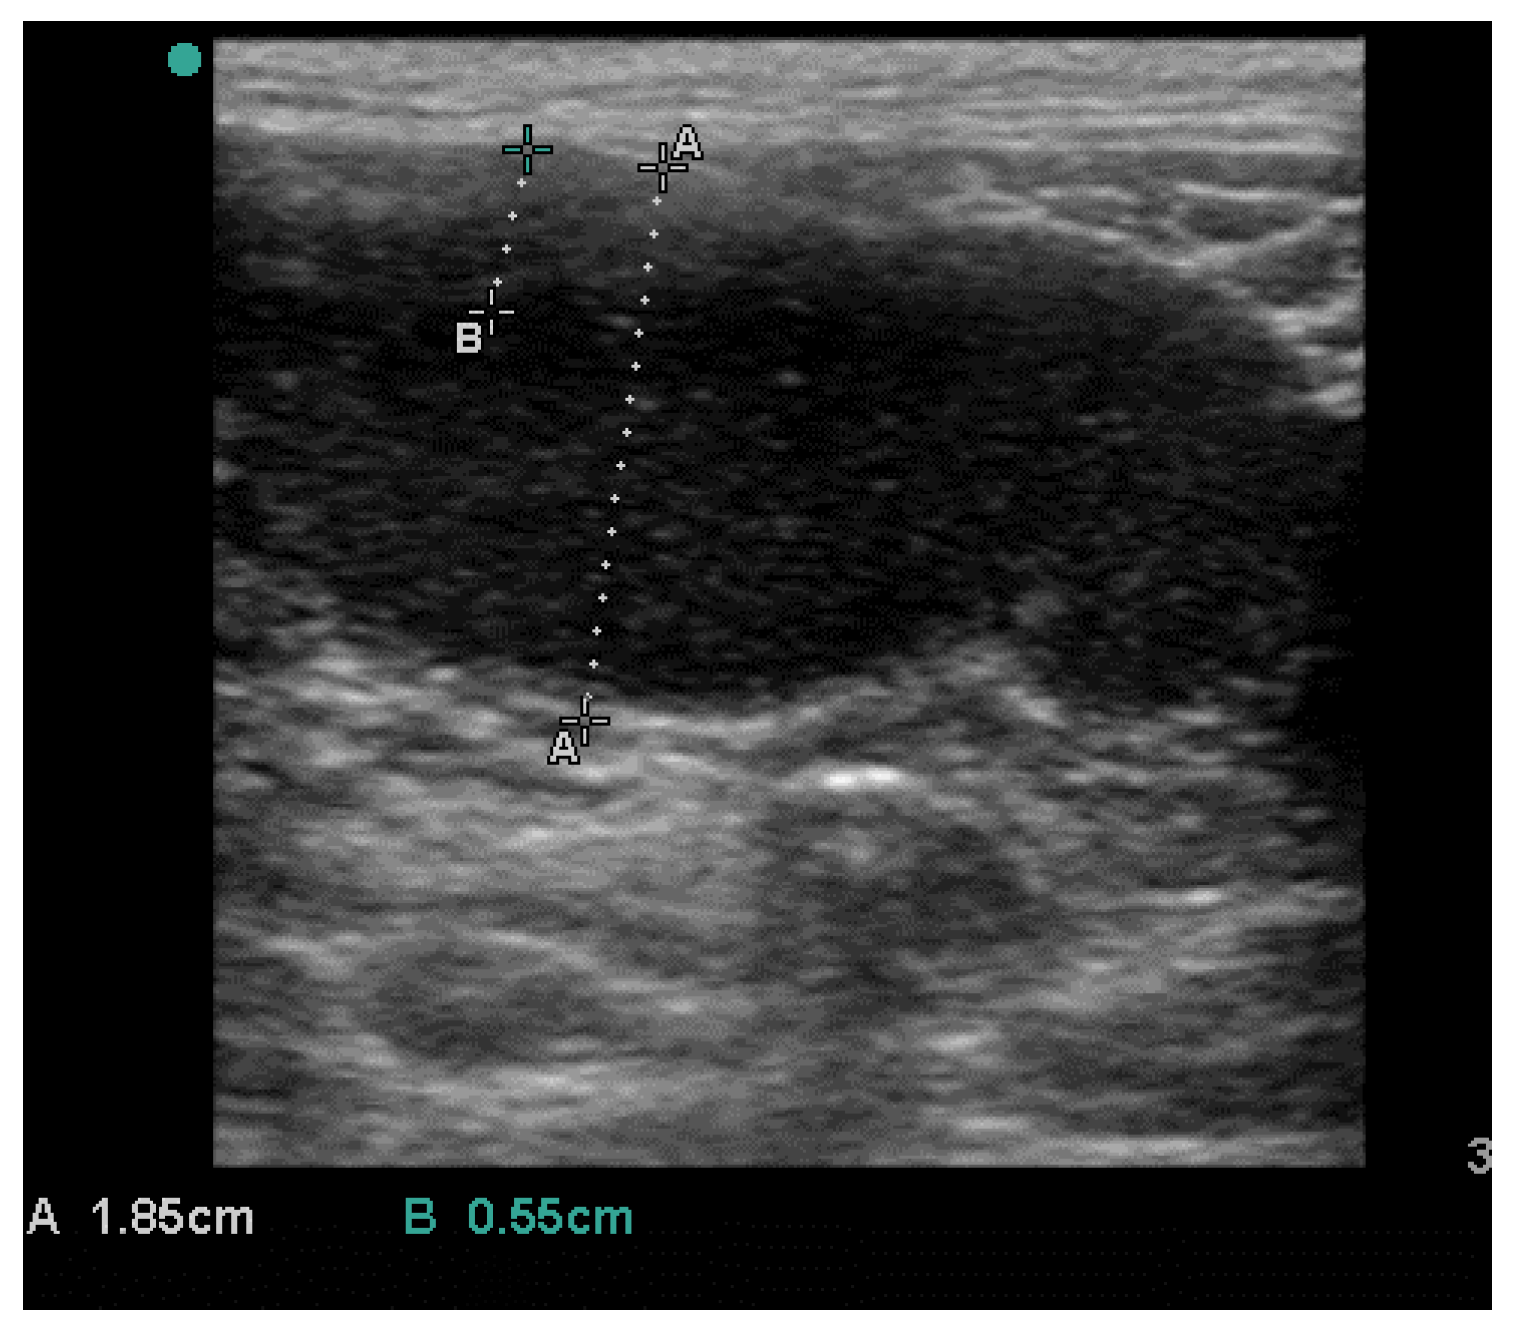

2. History and Clinical Findings

3. Treatment and Follow up